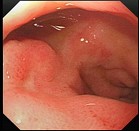

41、单项选择题 男性,22岁,反复解血便2月,无腹痛,无明显消瘦。一般情况可,无贫血,腹软,无压痛,未及包块,肠鸣音正常。

肠镜检查图片如下,最可能的诊断是()。

A.结肠息肉

B.结肠癌

C.Crohn病

D.结肠平滑肌瘤

E.结肠脂肪瘤

点击查看答案